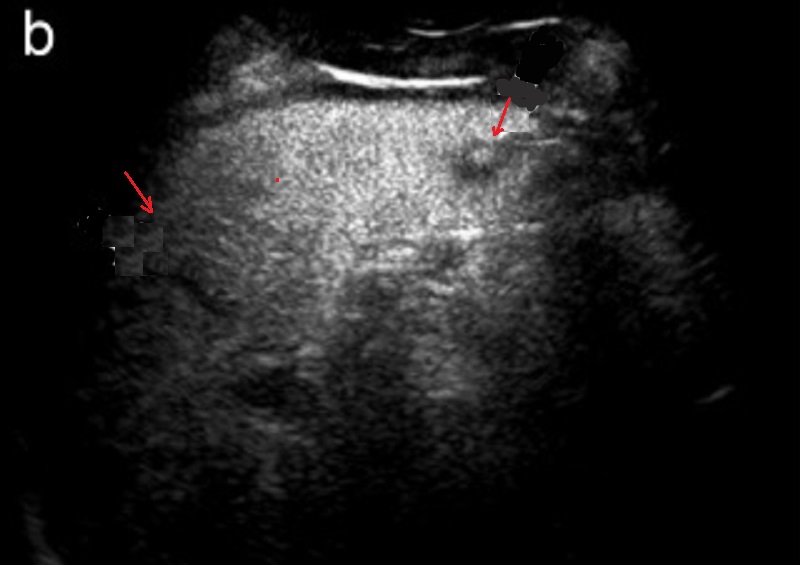

Image echographique des hematome intra-splenique

avec aspect lesionnel de zone hypoechogene mal limite ,

intra- parenchymateuse splenique ( fleche rouge ) |

Traumatisme de la rate avec

image echographique de multiple hematome a

hypoechogene dissemine intra-parenchymateuse (

fleche blanche ) |